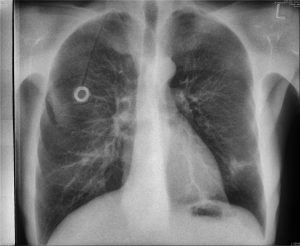

The case below showcases a traditional DR and two dual-energy X-ray images taken in a single exposure by Reveal 35C in PA view. While this example uses a PA view, Reveal 35C supports all imaging views — including lateral and oblique. From left to right: traditional DR, soft tissue, and bone image.

PA soft tissue image taken by single-exposure dual-energy X-ray system Reveal 35C

PA bone image taken by single-exposure dual-energy X-ray system Reveal 35C